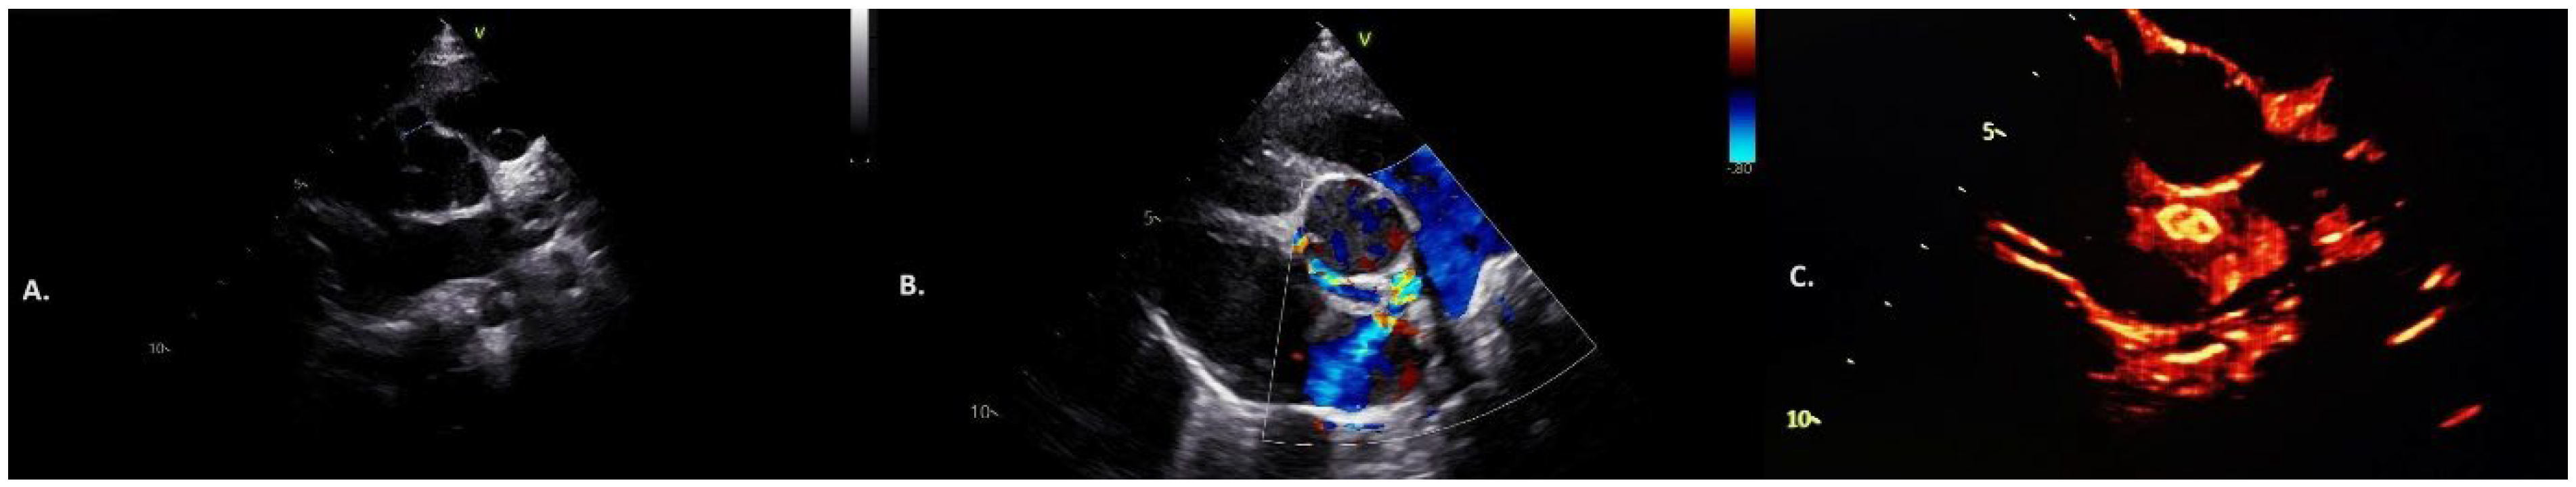

2. Case Report